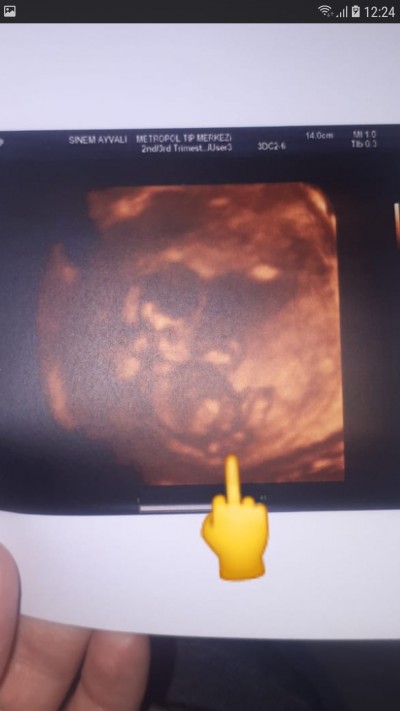

Kızlar ya doktora gittim bugn yine doktor sürekli cıkıntı var erkege benziyor diyor ama bisey diyemem diyo tecrübeli olanlar resime bakarak nolur soylermisiniz cok  merak ediyorum 2.cocugum şurda okla gosterdiğim yer top gibi onami diyor acaba çıkıntı diye

Orta parmak :D Valla sanki de erkeğe benziyor